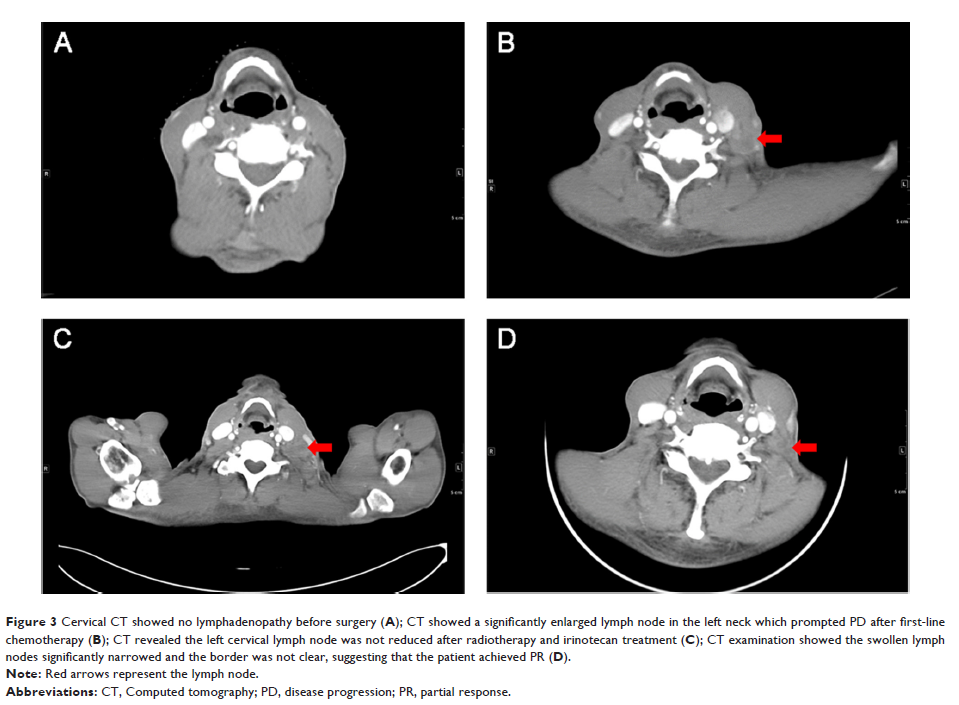

Case Report

阿帕替尼联合多西他赛治疗转移性食管鳞癌患者一例

- 作者:梁利军,闻艺璇,夏铀铀,王磊,费佳燕,蒋晓东

- 期刊:OncoTargets and Therapy